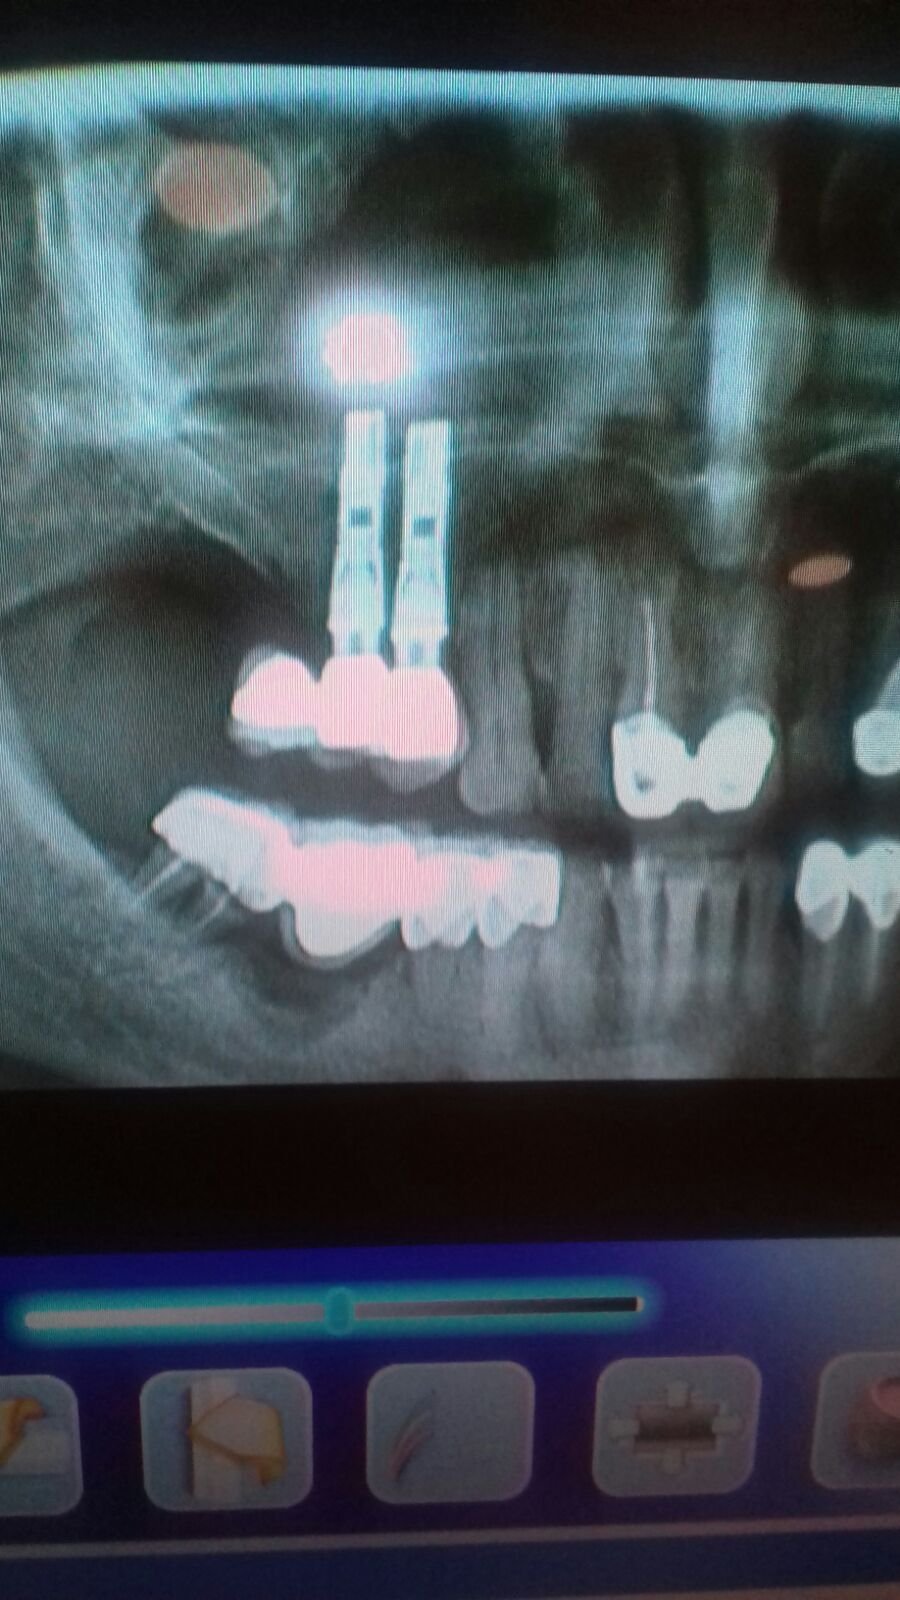

Hola, me gustaría saber la marca de estos implantes, y si es posible el sistema de bolas para sobredentadura, Gracias.